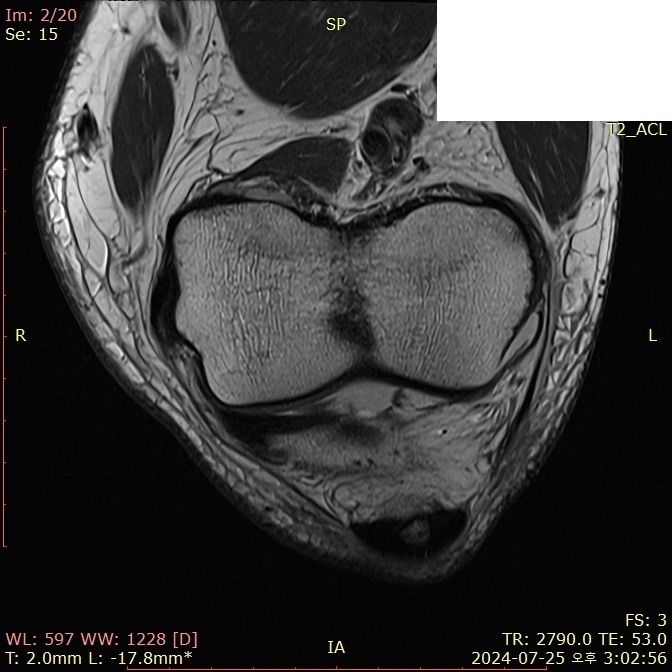

무릎 ACL(전방십자인대) 확인 부탁드려요

아스팔트에 무릎을 부딪쳐 심하게 부어서 mri 찍어봤는데 슬개골 비변위성 골절 판독 받은 건 기억 나는데, 인대는 기억이 잘 안나서 여쭤 봅니다..

전방십자인대 괜찮은가요...??ㅠㅠ

Mri에서 슬개골 비변위성 골절이 판독되었다면 일반적으로 전방십자인대에 대한 언급이 없다면 괜찮을 가능성이 큽니다. 하지만 정확한 진단은 의사와 상담을 통해 확인하는 것이 중요합니다.

전방십자인대 손상이 의심되면 추가적인 검사나 치료가 필요할 수 있습니다!